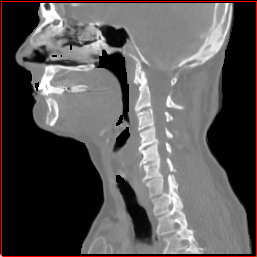

Head Region

1.1×1.1×1.11.1\times 1.1\times 1.1

mm

256×256×256256\times 256\times 256

Chest Region

1×1×11\times 1\times 1

384×384×384384\times 384\times 384

Abdomen Region

1×1×0.71\times 1\times 0.7

512×512×768512\times 512\times 768

Figure 3: MAISI-v2 segmentation-guided results for small to large volume size and three different regions.